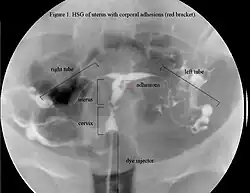

The history of a pregnancy event followed by a D&C leading to secondary amenorrhea or hypomenorrhea is typical. Hysteroscopy is the gold standard for diagnosis.[18] Imaging by sonohysterography or hysterosalpingography will reveal the extent of the scar formation. Ultrasound is not a reliable method of diagnosing Asherman's Syndrome. Hormone studies show normal levels consistent with reproductive function.

In an attempts to estimate the prevalence of AS in the general population, it was found in 1.5% of women undergoing hysterosalpingography HSG,[51] and between 5 and 39% of women with recurrent miscarriage.[52][53][54]